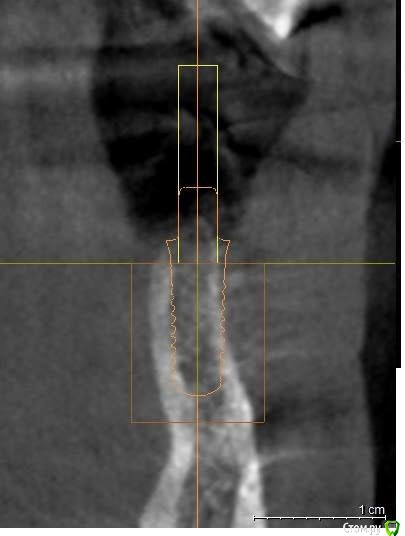

Astronaft Опубликовано 24 января, 2021 Поделиться Опубликовано 24 января, 2021 (изменено) Одиночный цирнокиевый имплантат и расщепление без графта. Пациентка:тонкая хрупкая женщина 55 лет, сконцентрированная на своем здоровье, в некоторой мере мнительная.всегда тяжелые заживления после удалений (по опросам)есть результаты Клиффорд теста (такая книжка под 200 страниц с in vitro аллерго-пробами на все известные материалы) Поставленная цель:только цирконий Мне было интересно найти вариант найболее приемленый пациентке и мне. С минимом хирургического риска и риском сожаления пациентки про выбор костного материала. Во-первых, я не использую аллографты - философски, чужие протеины, неприятный запах - просто основываясь на своем мнении.Во-вторых, мнительные пациенты склонны "пойти и почитать" до или потом и как следствие внушить себе вещи которых может и не было. Но по скольку мысль материальна... Все обсудил заранее.План: ридж сплит (расщепление), имплантат без графта, свободный СТ графт; если случается вестибулярная рецессия - пилим зирконий во рту. Ридж сплит сделан пьезотомом - крестальный и вертикальные пропилы на глубины около 8-10мм.Пилотное сверло.Развдвинул кость остеотомами от 1.6мм до 3.5мм в диаметре.Очень мягкая кость - напомнила мегкую максиллу плотности ногтевой пластинки вестибулярно.Имплант встал легко, но торк 40нсм. СТ графт из области 18. Деэпителизирую скальпелем уже потом. Тут интересно отметить, что я перестал боятся ошметков эпителия.Пончо сверху имплантата (а-ля шашлык Карлоса).Швы. PTFE всегда хорош. 12 недель.Красивая десна.Периотест -5.8 - отличный результат.Оттиск. Циркониевая коронка симметричная другой стороне. Изменено 24 января, 2021 пользователем Astronaft 19 Ссылка на комментарий

Astronaft Опубликовано 25 января, 2021 Автор Поделиться Опубликовано 25 января, 2021 Спасибо.День операции, 12 недель, день цементировки. 3 1 Ссылка на комментарий